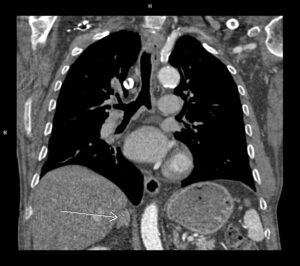

Figura 1: axial angioCT arterial orificiul de intrare proximal

Discuţie caz nr 126: Investigația CT a fost realizată pentru control postoperator la un pacient cu proteză de aorta ascendentă pentru disecție de aorta Stanford tip A operată. Se evidențiază proteză de aortă ascendentă în poziție normală, fără dezvoltări anevrismale la nivelul anastomozelor precum și disecție de aorta toracică și abdominală restantă cu orificii de intrare proximal precum și distal în vecinătatea originii arterei renale drepte, iar faldul de disecție nu evoluează la nivelul ramurilor. În plus, se evidențiază stenoză proximală de trunchi celiac cu dilatație poststenotică